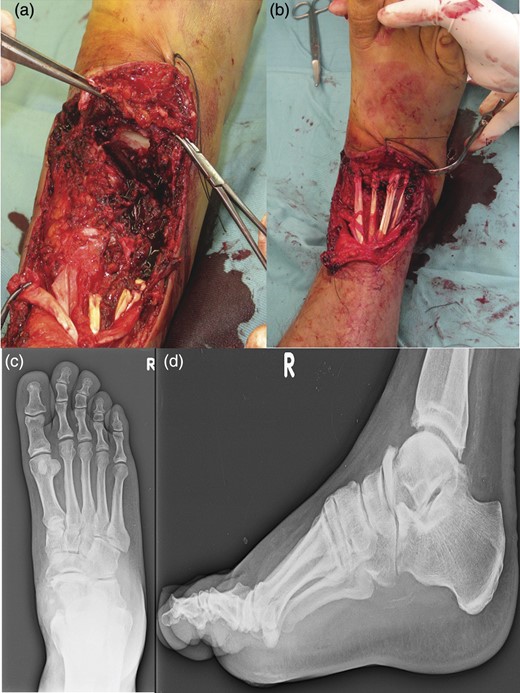

The patient underwent a first-time surgical repair. Abundant washing of the lacerated wound with saline solution and chlorhexidine was done. Injuries of dorsalis pedis artery, tibialis anterior tendon, estensor digitorum longus tendons, peroneus tertium tendon were revealed, with the loss of talus head and with a complex lesion of the talonavicular ligament. Tendinous structures damaged were surgically sutured and subsequently an antibiotic-loaded cement spacer was positioned into the bone gap to re-establish the joint congruence. The foot was put in a cast and kept non-weight bearing for 8 weeks (Fig. 2).

An image of the foot before the first-time surgical repair reveals the injuries of dorsalis pedis artery, tibialis anterior tendon, estensor digitorum longus tendons, peroneus tertium tendon, with the loss of talus head and with a complex lesion of the talonavicular ligament. (a) Tendinous structures damaged were surgically sutured and subsequently an antibiotic-loaded cement spacer was positioned into the bone gap to reestablish the joint congruence (b). AP (c) and lateral (d) radiographs of the foot in the cast after the surgical time.